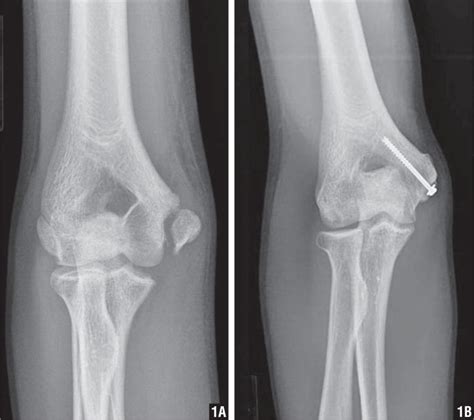

Diagnosis is made with plain radiographs of the humerus and elbow. Medial epicondylar fractures are the third most common fracture seen in children and are usually seen in boys between the age of 9 and 14. The ulnar nerve runs in a groove on the back of this epicondyle. Distal humerus fractures are traumatic injuries to the elbow that comprise of supracondylar fractures, single column fractures, column fractures or coronal shear fractures. A posterior band, which is stressed during elbow flexion;

23 Distal Humerus Fractures | Musculoskeletal Key

23 Distal Humerus Fractures | Musculoskeletal Key from i0.wp.com